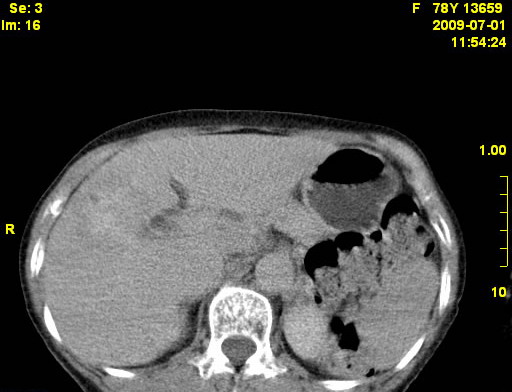

以下是引用zjzjr在2009-7-3 11:02:00的发言:[br]动脉期不均匀强化,门脉期及延迟期强化明显,肝门部见肿大淋巴结影,肝内胆管扩张.考虑肝右叶前段胆管细胞癌伴肝门淋巴结转移,胆内胆管扩张.慢性胆囊炎.

以下是引用dsl555在2009-7-4 10:59:00的发言:[br]考虑肝右叶前段胆管细胞癌伴肝门淋巴结转移,胆内胆管扩张.慢性胆囊炎. [br][br]支持。